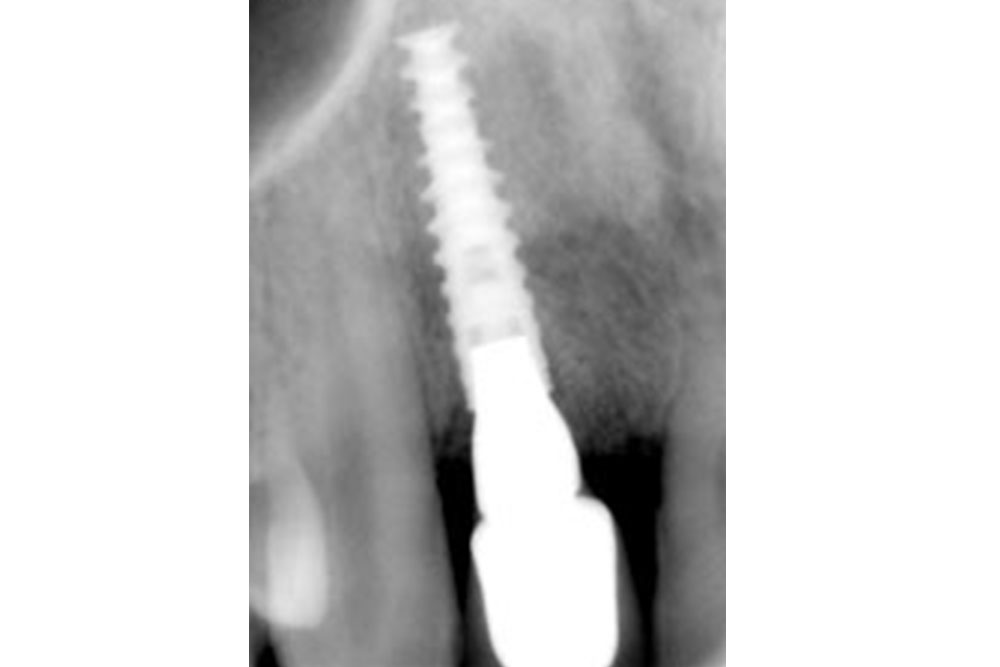

右上の2番目の歯の周りの骨が下がってきてしまい、歯がグラグラになり、抜歯をしなければならない状態でした。抜歯をした直後にその部位にインプラントの埋入オペを行いました(抜歯即時埋入)のでオペは1回で済みました。

インプラントにはすぐに仮歯を装着しましたので(即時負荷)治癒期間も不自由なく快適に過ごせます。

インプラントの上にアバットメント(ジルコニア)を装着した状態。